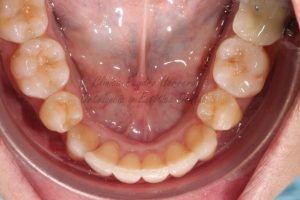

- Conseguimos enderezar todos los ángulos dentales que estaban inclinados.

- Abrimos las arcadas para lograr una forma final parabólica y redondeada.

- Engranamos perfectamente todos los dientes.

Con el tratamiento de ortodoncia finalizado y el apiñamiento severo corregido, pasamos a la segunda fase de estética dental. En dicha fase realizamos en primer lugar un blanqueamiento dental para devolver a los dientes un aspecto mucho más saludable, estético y brillante. Tras el blanqueamiento realizamos unas microcarillas de composite con las que conseguimos cerrar los pequeños diastemas existentes entre los incisivos superiores.